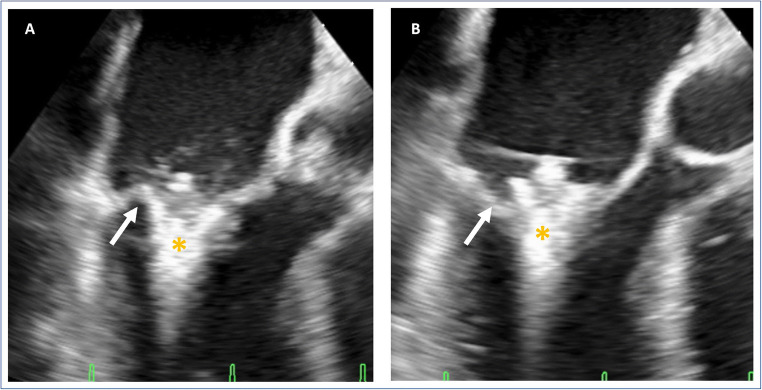

Fig. 3.

Perforation. Presentation of an intraprocedural leaflet perforation during grasping. A Transesophageal commissural view demonstrating the grasp of the leaflet showing the posterior leaflet (arrow) still on the clip (*). B Transesophageal commissural view showing the perforated posterior leaflet (arrow). *MitraClip